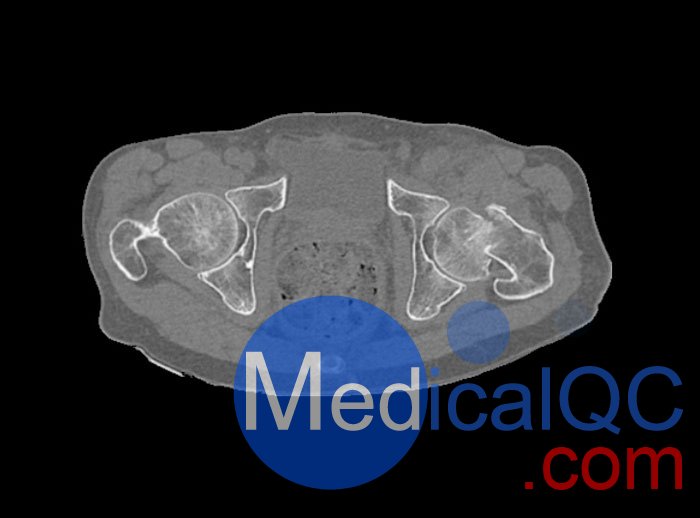

WEK54-01股骨頸骨折骨盆模型,WEK54-01骨盆模體模擬沒有靜脈造影劑的骨盆(天然)。它覆蓋了整個骨盆,直到第五腰椎。

左側股骨頸移位骨折。

該模型可用于 CT(包括 CBCT)和射線照相,以評估和優化成像性能和后處理應用,包括支持 AI 的應用。它也適用于培訓目的。

WEK54-01股骨頸骨折骨盆模型,WEK54-01骨盆模體提供了對軟組織和骨組織的詳細而逼真的模擬。空隙中填充著約-160HU的纖維素-聚合物復合材料。

骨骼和軟組織的逼真模擬。

WEK54-01股骨頸骨折骨盆模型,WEK54-01骨盆模體成像效果圖: